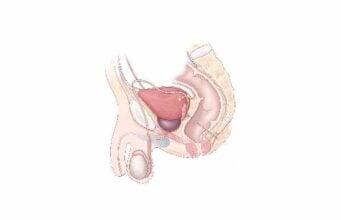

Discover the wonders of the human body, from its fundamental elements to the intricate systems that sustain life. This section explores the anatomy, physiology, and functions of various body parts, providing insights into our movements, thoughts, emotions, and interactions with our surroundings.